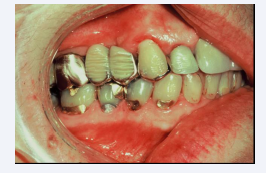

Non-Carious Lesions (NCLs)

These deformations, aka sets, are multi-shaped examples of hard tissue fatigue due to compression failure. Fatigue applies to changes in the properties of a material due to repeated applications of stress or strain-in this case, compression failure from DCS. If an object, such as a tennis ball, rebounds to its original shape after repeated compressions, it is said to be elastic in nature. However, if an object exhibits residual defects after repeated compression, it is said to be plastic in nature. Biological structures, such teeth and bone are termed viscoelastic and are subject to deformation. Engineers refer to this type of fatigue as corrosion fatigue (Figure 1) [3].

Figure 1 Non-Carious Lesions (NCLs)

Figure 1: Non-Carious Lesions (NCLs)